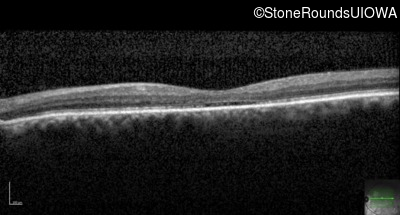

Age at visit: 59 years

This 65 year old man has had nystagmus since birth. His acuity was never better than 20/80 in either eye. He has significant photophobia in normal office light but sees normally in very dim light. His color vision is also poor. He cannot recognize any of the Ishihara color plates.